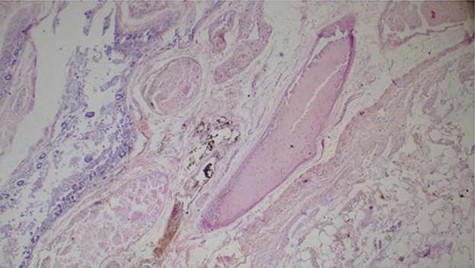

Histopathology analysis of the lung specimens revealed mixed chronic inflammatory infiltrates associated with pulmonary vascular thrombosis and areas of extensive necrosis (Figs 3 and 4). Bowel tissue sections revealed severe ischemic necrosis and mesenteric vessel thrombosis (Fig. 5). Thus, the primary causes of death were ruled to be ischemic colitis and pulmonary thrombosis due to COVID-19. The underlying disease conditions contributing to the cause of death being hypertensive heart disease, diabetes mellitus and septicemia.

Histopathology of lung tissue showing vascular thrombosis and extensive fibrosis and necrosis (hematoxylin and eosin ×40).